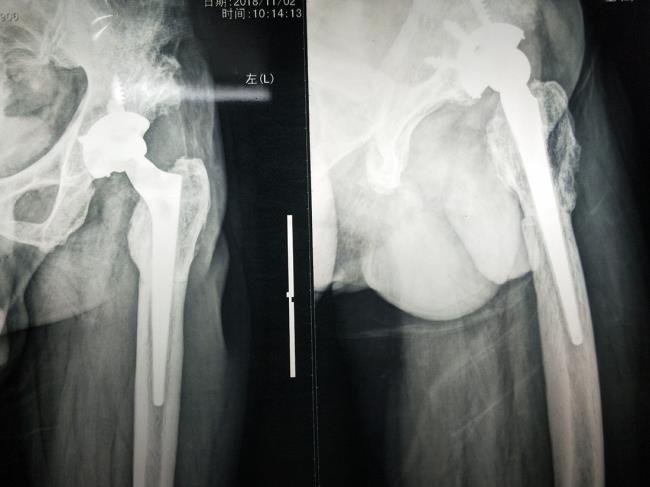

开展人工髋、膝关节置换手术